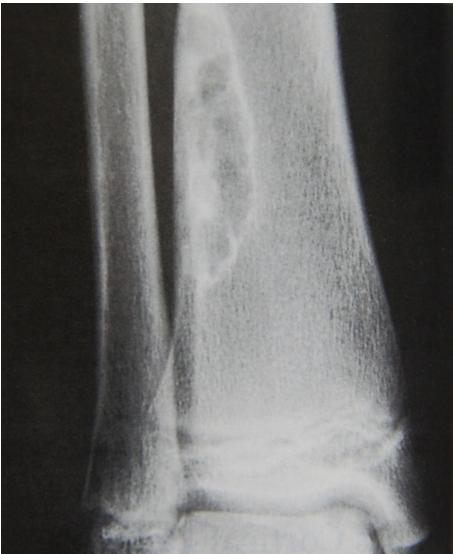

site: Diaphyseal, metaphysal size: partial matrix: Mixed - Narrow zone of transition, well defined, syndosmosis soft tissue involvement: No tissue involvement